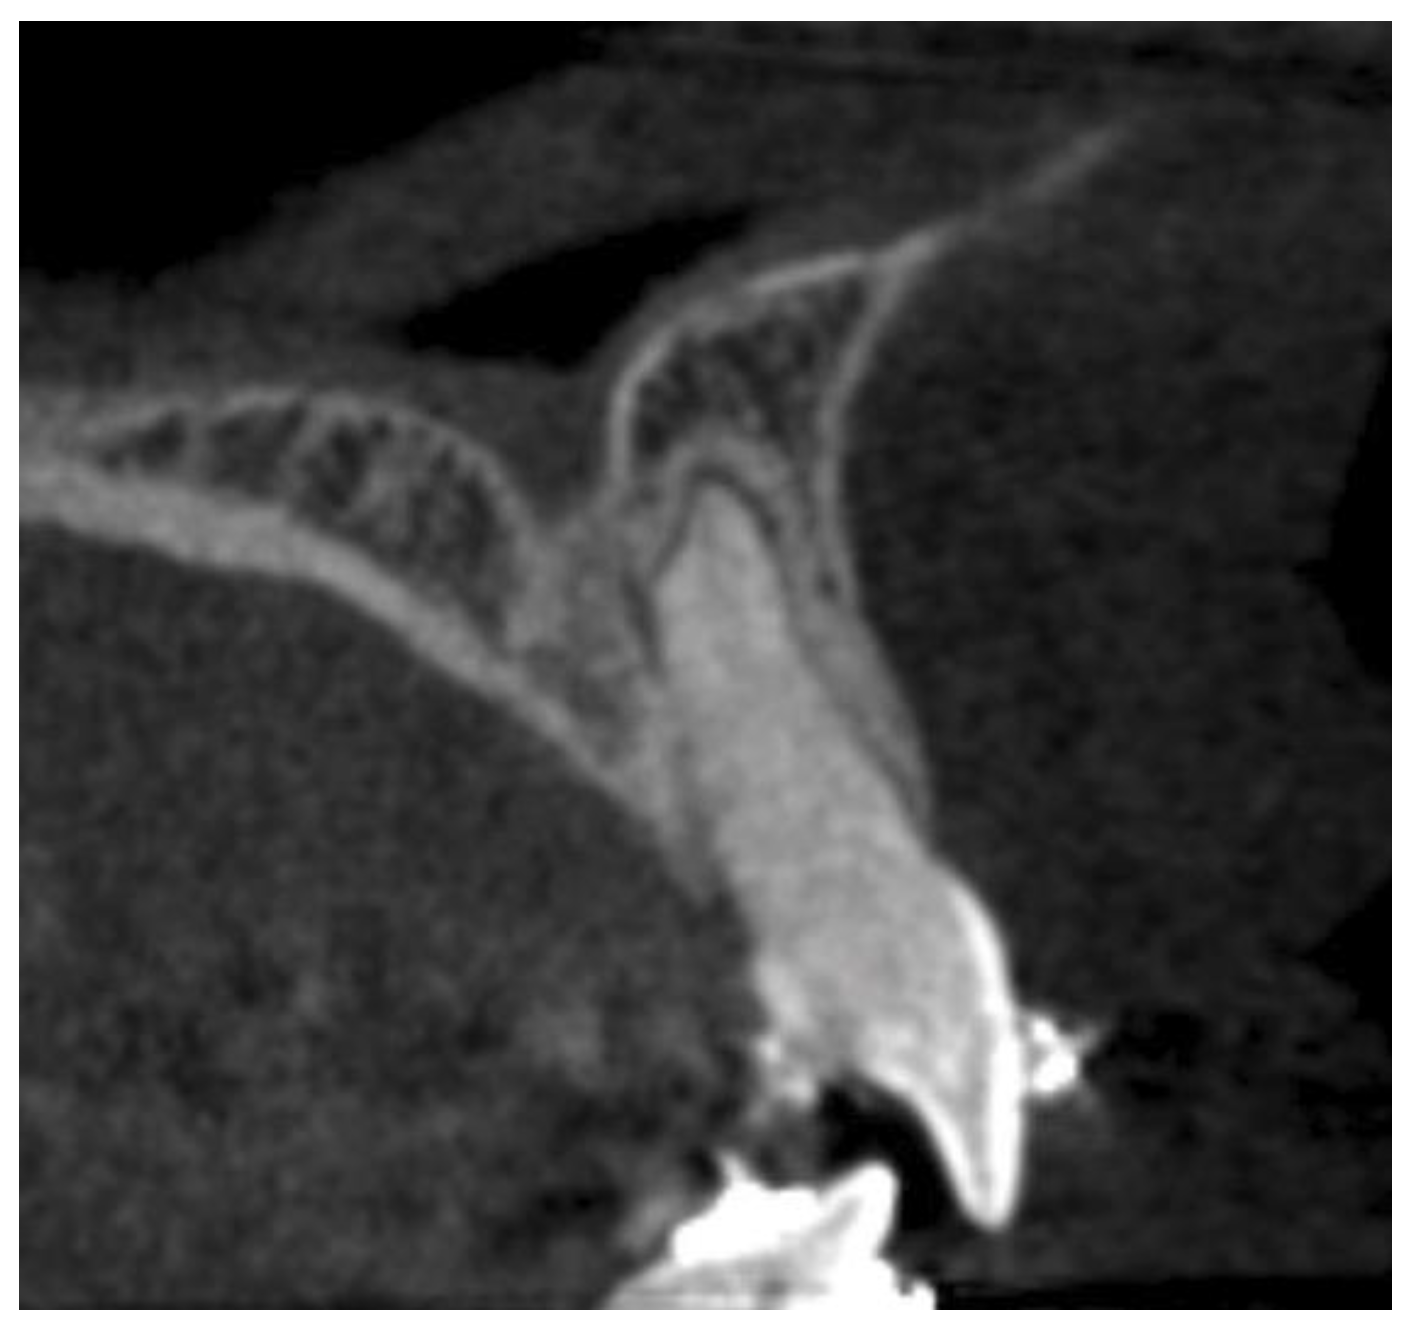

2.2. Data Acquisition and Measurements

- Horizontal plane separately for each level—L1, L2, and L3:

- Incisive canal width—|Cl-Cl|.

- Antero-posterior IC—|Ca-Cp|.

- Distance between the most mesial point of the root and the tangent passing through the most anterior point of the incisive canal—|Rm-Cat|.

- Distance from Cl to the posterior edge of the incisor root—|Cl-Rpt|.

- Distance between roots |Rm-Rm|.